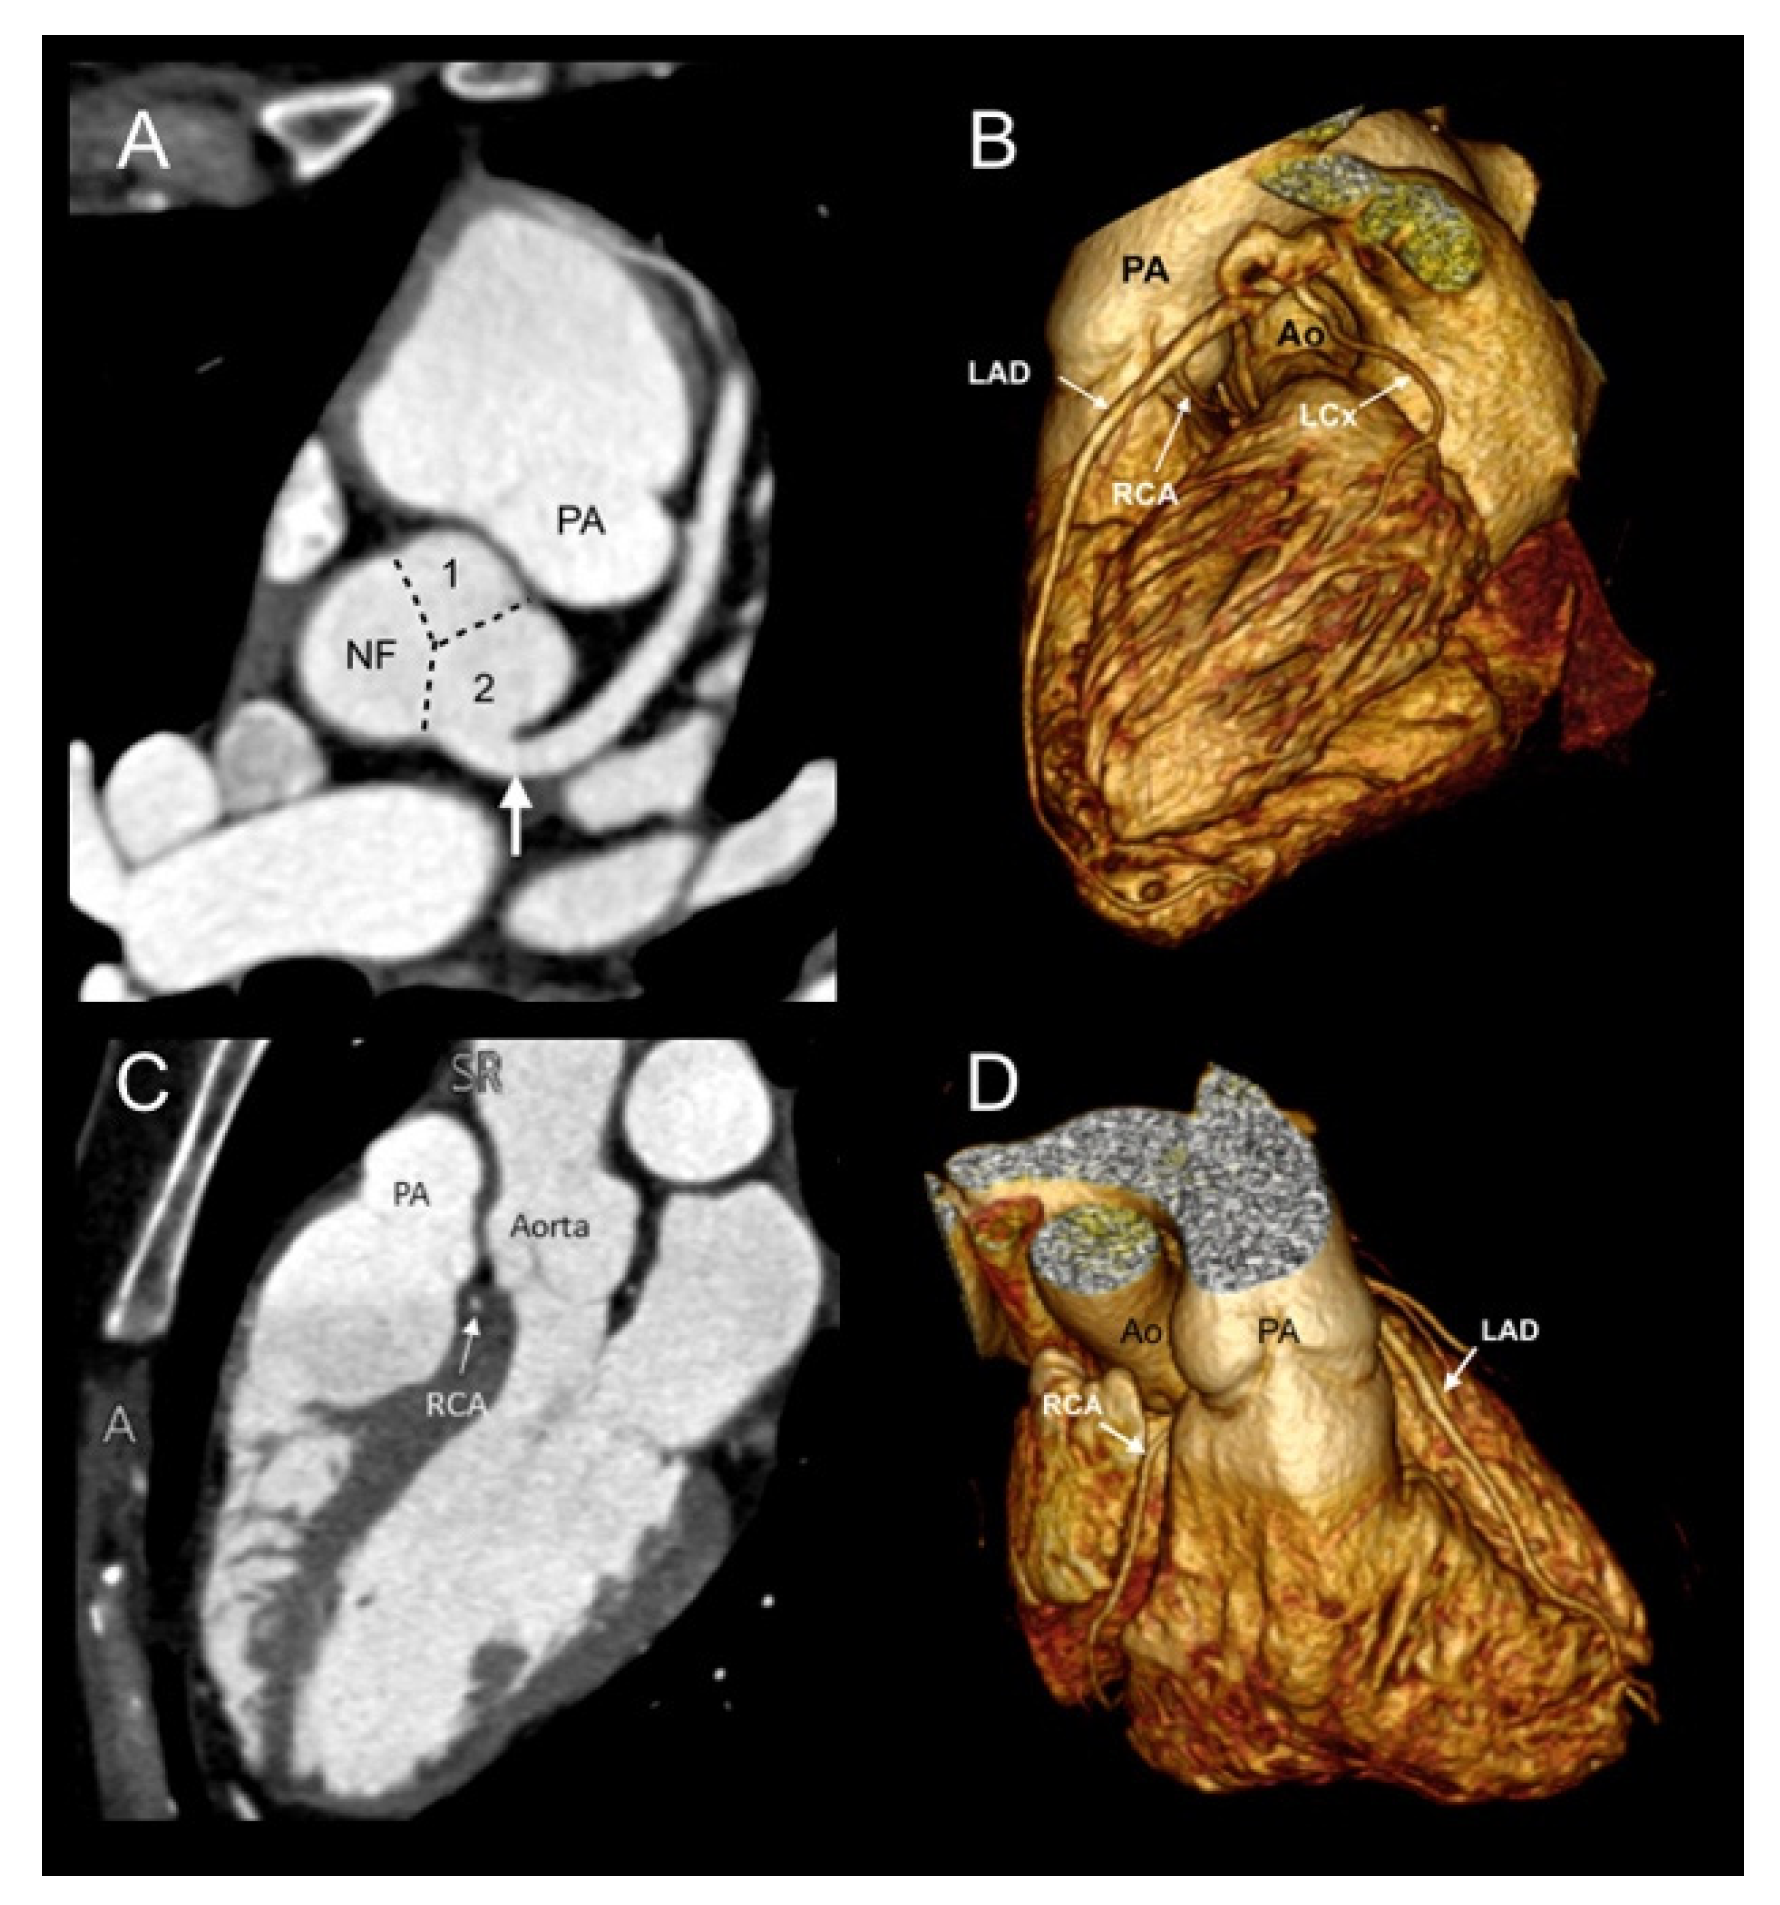

3.1. Lipton Classification

3.2. Leiden Convention Coronary Coding System